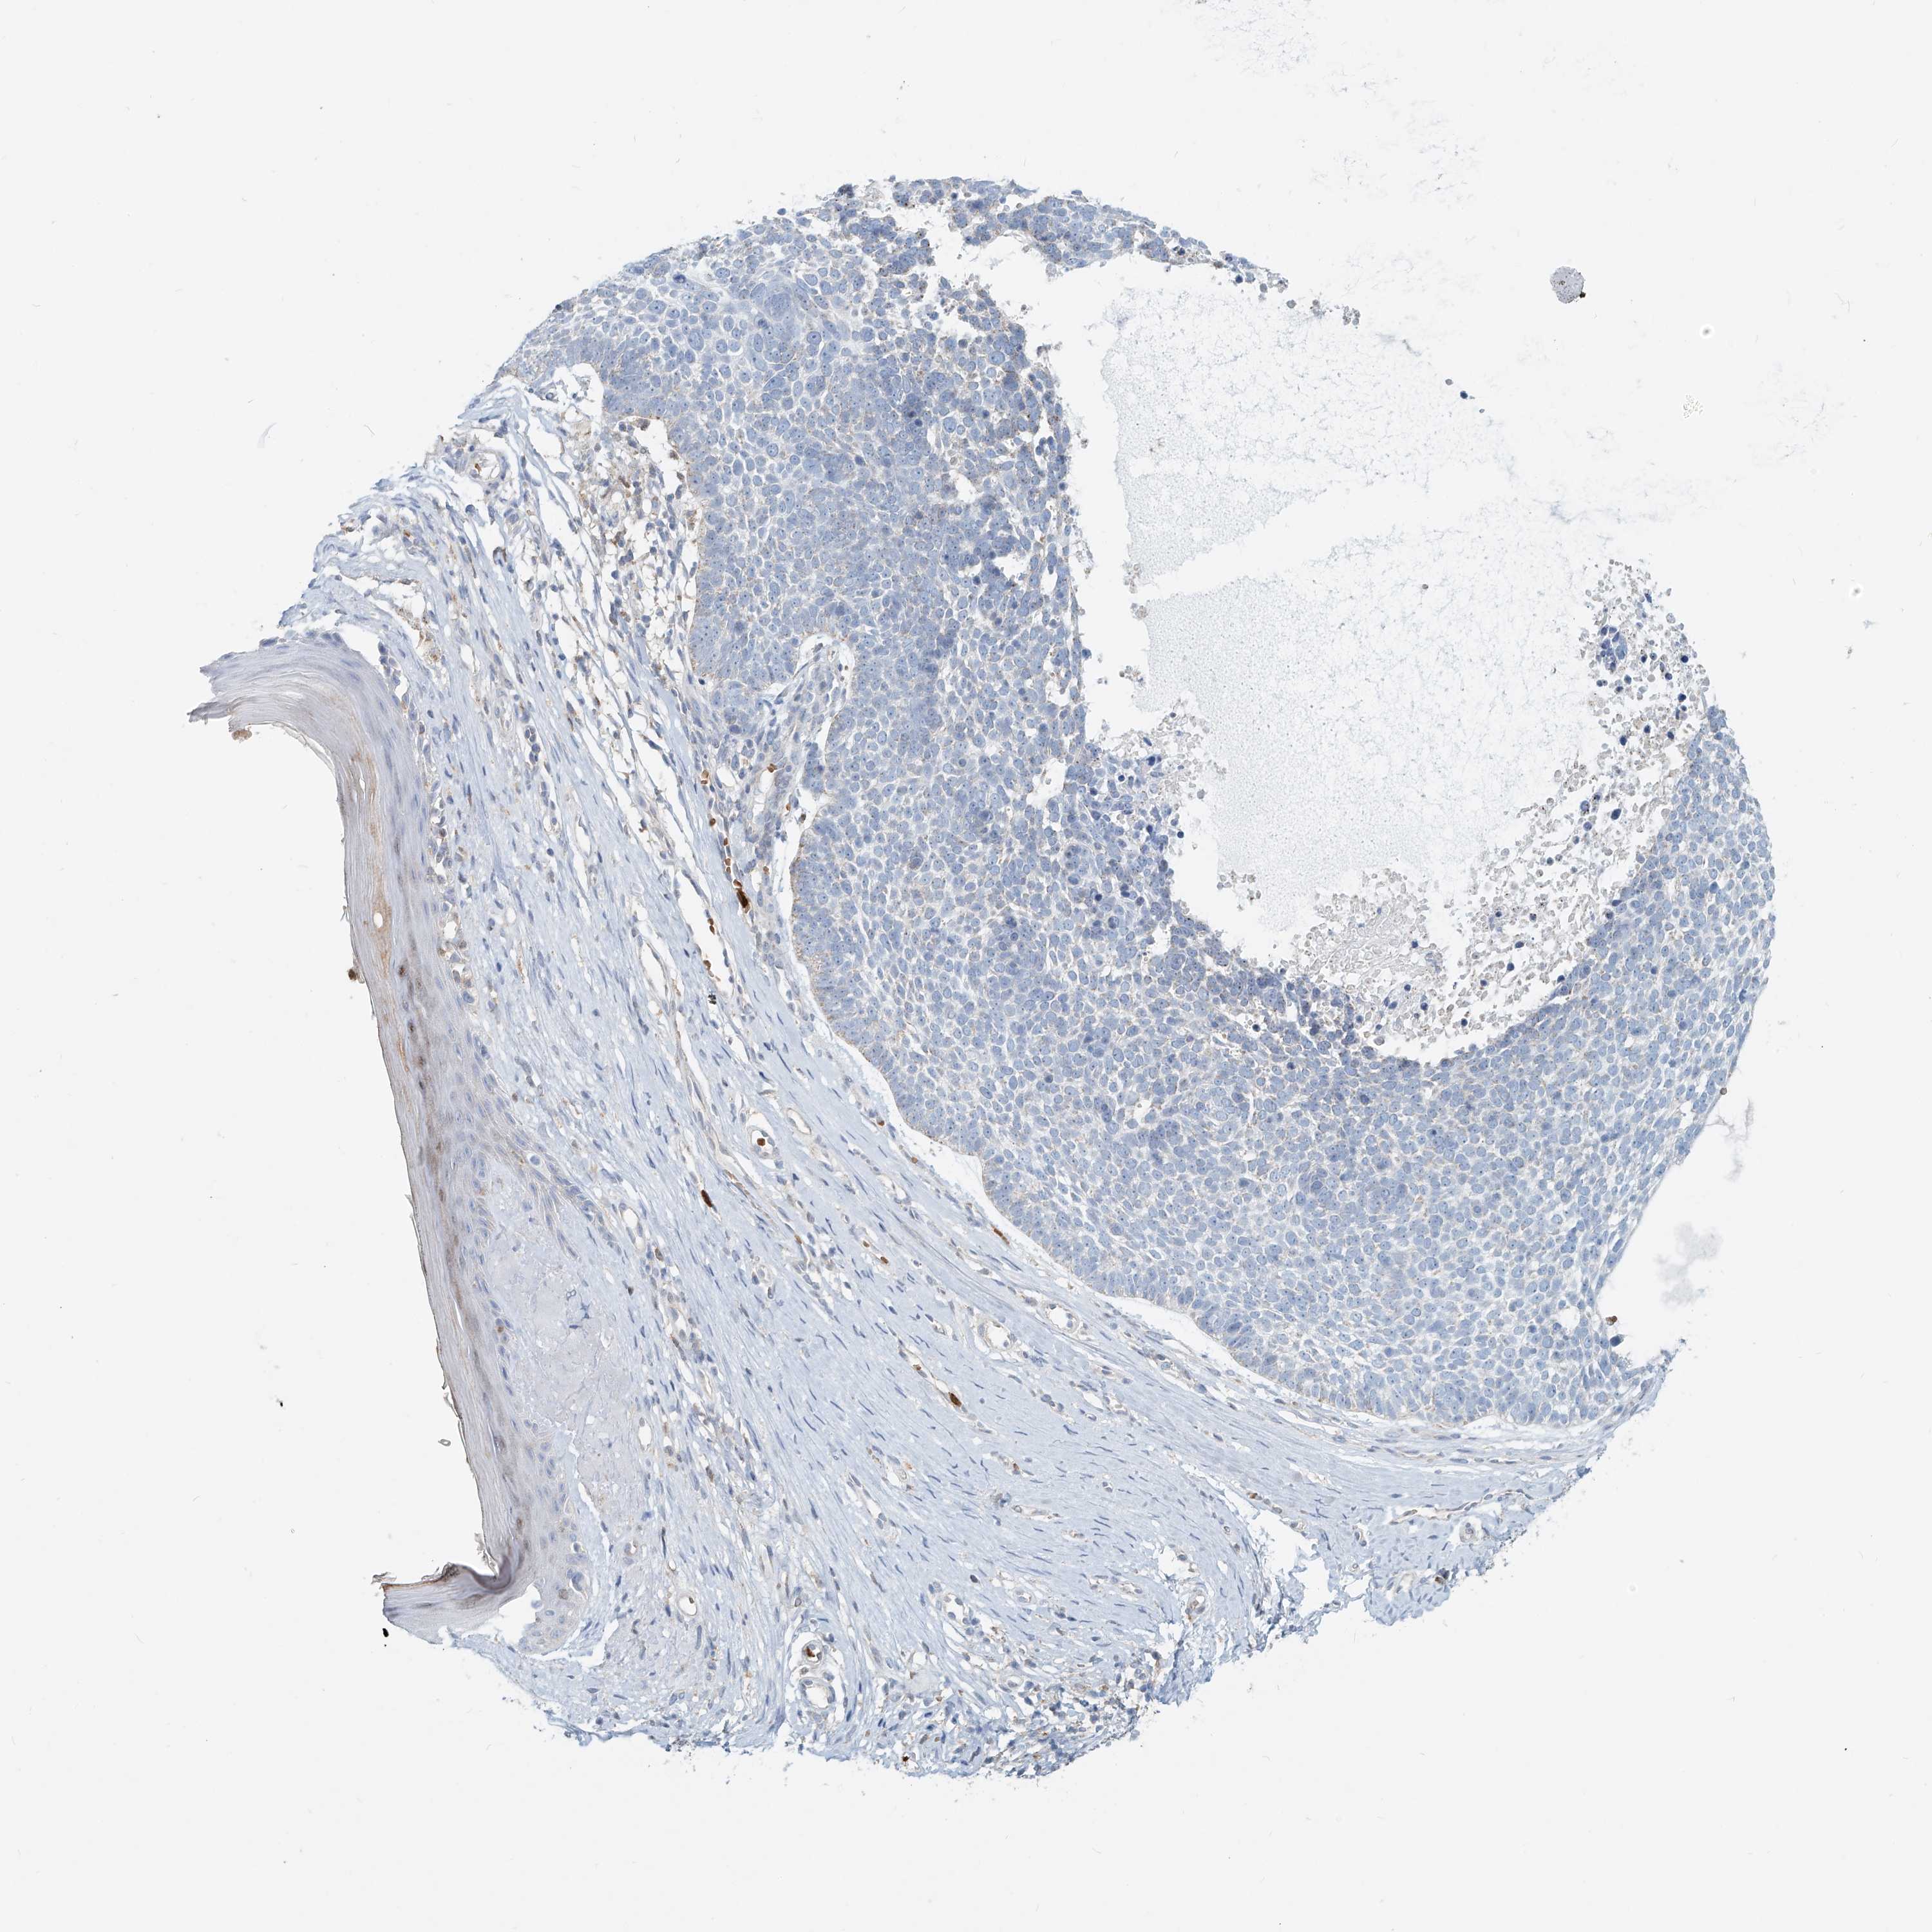

CANCER SKIN CANCER Show tissue menu

Basal cell and squamous cell cancer

SKIN CANCER - Protein expressioni

A mouse-over function shows sample information and annotation data. Click on an image to view it in a full screen mode. Samples can be filtered based on level of antibody staining by selecting one or several of the following categories: high, medium, low and not detected. The assay and annotation is described here.

Each image is clickable and will lead to virtual microscopy that enables deeper exploration of all samples and also displays staining intensity scores, fraction scores and subcellular localization as well as patient and tissue information for each sample.

Antibody HPA029412

Antibody CAB034366

Basal cell carcinoma

Squamous cell carcinoma, NOS

Squamous cell carcinoma, metastatic, NOS